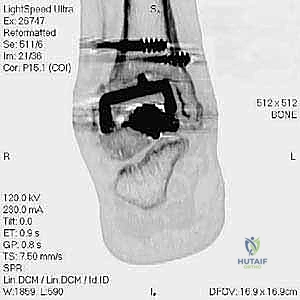

مراجعة مفصل الكاحل الصناعي هي إجراء جراحي ضروري لمعالجة المشاكل التي قد تنشأ بعد الجراحة الأولية، مثل كسور الكعبين أو عدم استقرار المفصل. يتضمن العلاج التشخيص الدقيق عبر الأشعة السينية والتصوير المقطعي، يليه التدخل الجراحي لتثبيت الكسور واستعادة وظيفة الكاحل، مع التركيز على التعافي المبكر.

تُعد جراحة مراجعة مفصل الكاحل الصناعي (Revision Total Ankle Replacement) من الإجراءات الجراحية المتقدمة والبالغة الدقة في عالم جراحة العظام الحديثة. لا تقتصر هذه الجراحة على مجرد استبدال مفصل تالف بآخر جديد، بل هي عملية إنقاذ معقدة للغاية تهدف إلى معالجة المشاكل الميكانيكية والبيولوجية التي تنشأ بعد الجراحة الأولية. من أبرز هذه المشاكل: الفشل الميكانيكي للمفصل، تحلل العظام (Osteolysis)، أو حدوث كسور معقدة في الكعبين (Malleolar Fractures) المحيطة بالمفصل الصناعي. يتطلب هذا الإجراء تقييماً سريرياً وشعاعياً دقيقاً يشمل التصوير المقطعي ثلاثي الأبعاد والأشعة السينية، يليه تدخل جراحي دقيق لاستعادة التوازن الحيوي والميكانيكي للكاحل والحفاظ على الطرف من البتر أو الدمج.

- التصوير المقطعي المحوسب (CT Scan): وهو الأداة الذهبية لتقييم "المخزون العظمي" (Bone Stock). يوضح بدقة حجم الأكياس العظمية ومقدار العظم المفقود الذي سيحتاج لترقيع.

علاج هذه الكسور يتطلب مهارة فائقة من الدكتور محمد هطيف، حيث يتم استخدام تقنيات الجراحة الميكروسكوبية وتثبيت الكسور باستخدام صفائح معدنية دقيقة ومسامير (Locking Plates) دون المساس بثبات المفصل الصناعي، أو يتم دمج علاج الكسر ضمن عملية مراجعة المفصل الكلية إذا كان المفصل نفسه تالفاً.